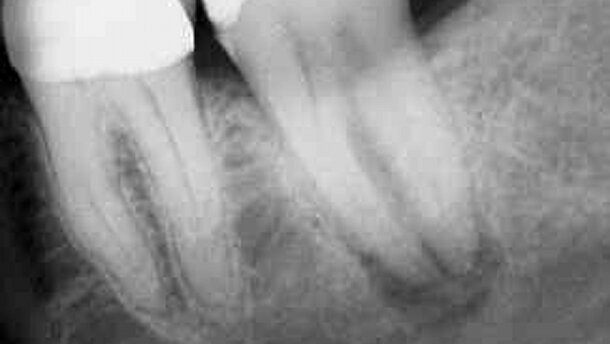

Une patiente âgée de 48 ans m’a été adressée pour l’évaluation et le traitement d’une douleur localisée à la deuxième molaire inférieure gauche (dent 37). La patiente a expliqué avoir souffert récemment d’une douleur extrêmement lancinante dans la région de cette molaire. La douleur irradiait jusqu’à l’oreille gauche et avait duré trois jours consécutifs. La patiente a également expliqué que son chirurgien-dentiste avait réalisé un traitement du canal radiculaire après une préparation cavitaire (Fig. 1), quelques mois avant de me consulter. L’examen a révélé une sensibilité à la percussion et à la palpation, et une profondeur du sillon gingivo-dentaire autour de la dent 37 n’excédant pas 3 mm. L’examen radiographique a indiqué un échec endodontique, associé à une radioclarté périradiculaire (Fig. 2).

La patiente a été anesthésiée et la dent 37 a été extraite et placée dans une éponge de gaze stérile, saturée d’une solution saline. La plaie a été recouverte d’une compresse de gaze stérile et il a été demandé à la patiente de serrer les dents, afin d’immobiliser la compresse. Une résection des racines mésiales et distales a été réalisée, en biseautant l’apex radiculaire avec une fraise 702, montée dans une pièce-à-main droite. La racine mésiale a été préparée à rétro, à l’aide d’une fraise boule 1/2 montée sur un contre-angle, en présence d’une irrigation abondante. Les canaux radiculaires ont été obturés à rétro avec du MTA (Fig. 3). La procédure extrabuccale étant terminée, l’alvéole a été délicatement irrigué avec une solution saline normale pour éliminer le caillot, et la dent a été réimplantée. Aucune contention n’a été nécessaire. Six semaines plus tard, la patiente ne présentait plus aucun symptôme et la dent réimplantée était stable dans son alvéole. Nous avons dès lors recommandé à la patiente d’entreprendre la restauration définitive de la molaire réimplantée (Figs. 4–8). Après un an (Fig. 9), trois ans (Fig. 10), quatre ans (Fig. 11) et huit ans (Fig. 12), la patiente est revenue pour une évaluation et la dent a été radiographiée. Les clichés n’ont indiqué aucun signe de résorption et la patiente était asymptomatique.